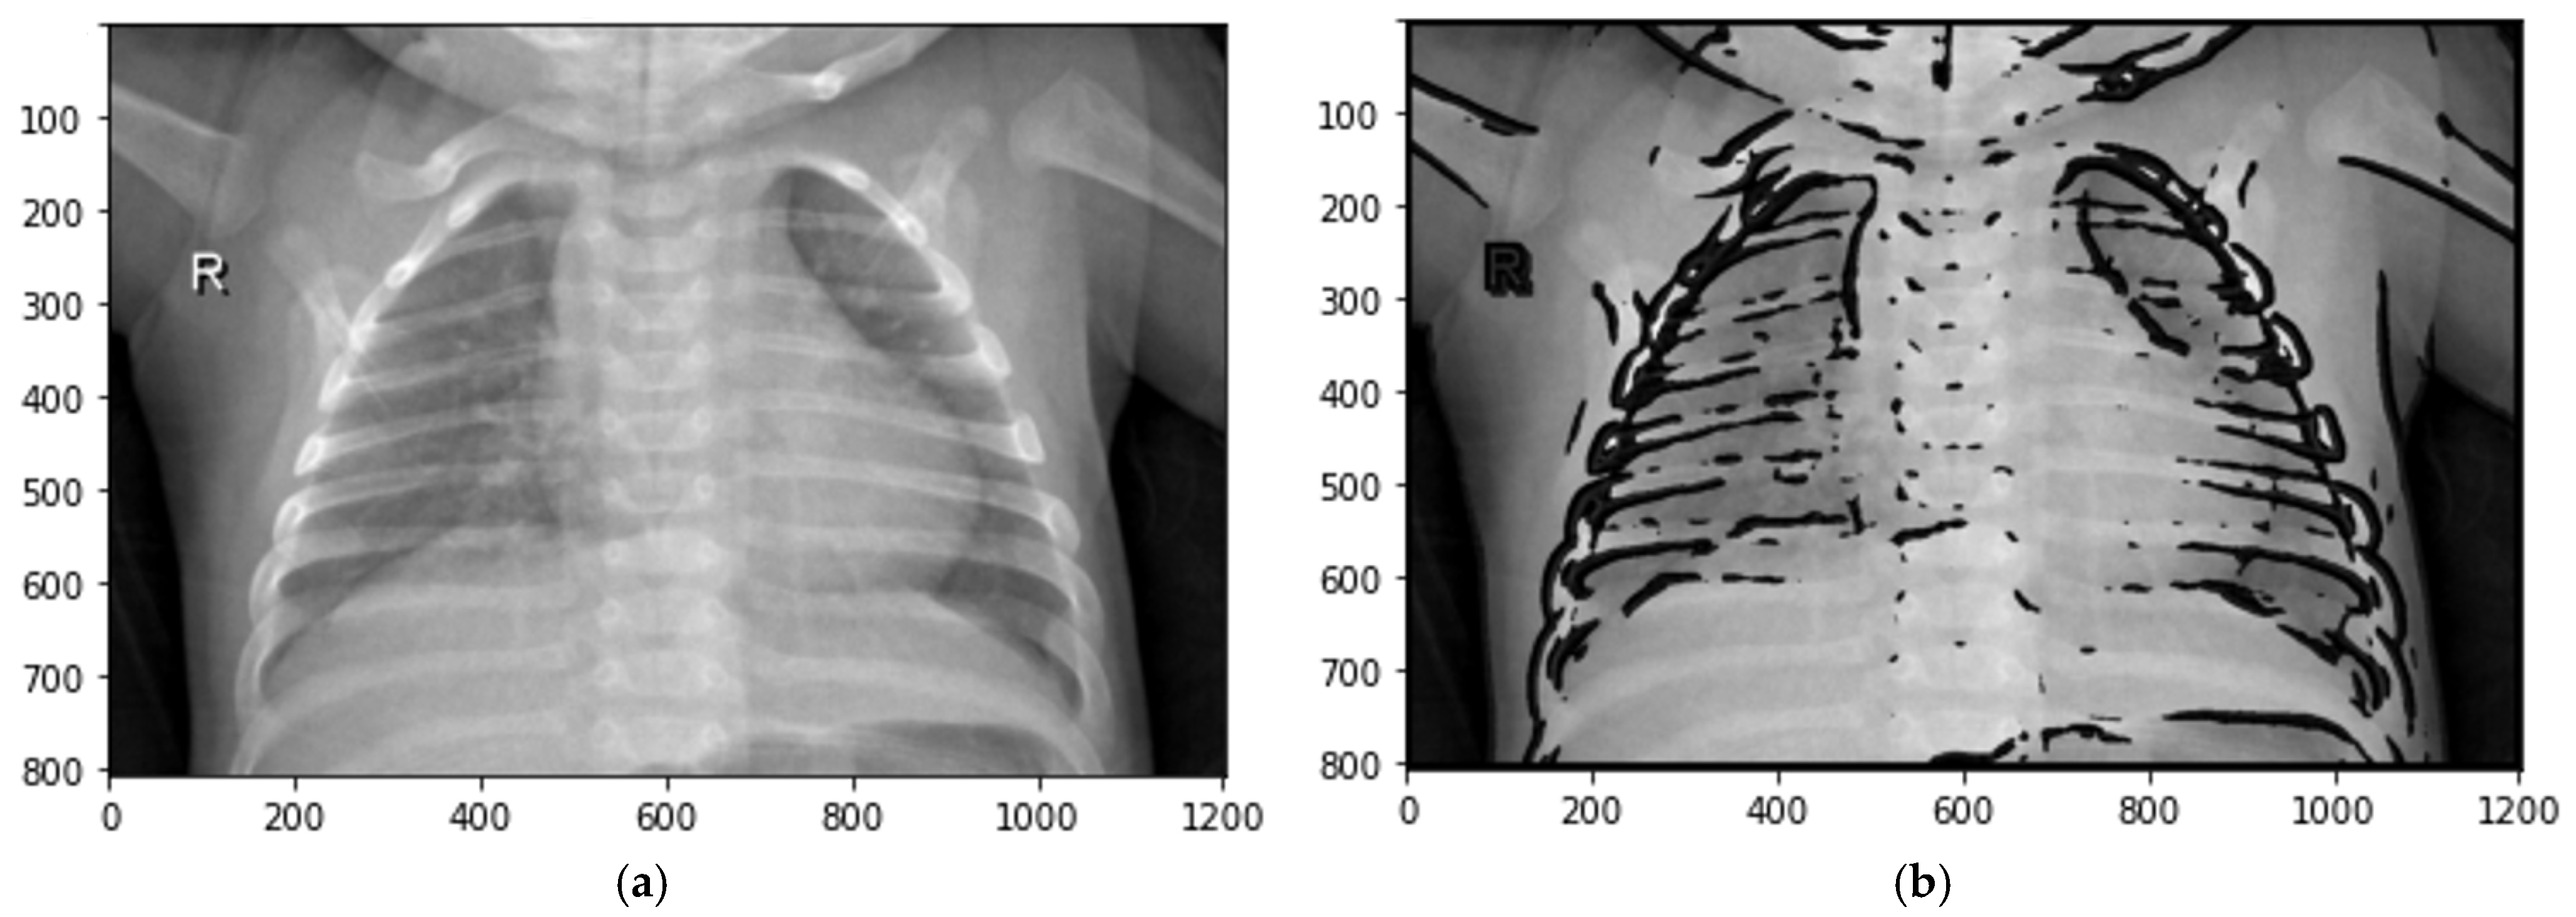

where s > 0. See Figure 5.

Figure 5.

Transformation of local contrasts by fuzzy entropy: (a) original image; (b) defuzzified image.